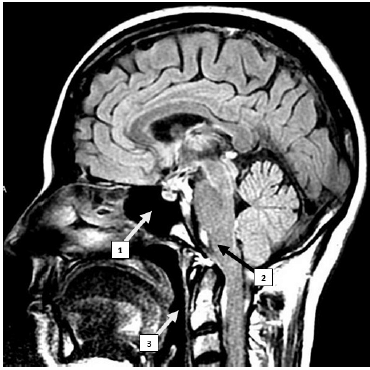

Internet: <cdiumuarama com br/exame/> Figura 3

Tendo como referência a imagem precedente, julgue o item que se segue.

A estrutura indicada pelo número 3, denominada faringe, é um órgão tubular com início logo após as coanas e possui, na sua terminação, comunicação com a laringe e o esôfago.

Enunciado 1181772-1

Para indicar a posição de estruturas na vertical localizadas no esqueleto axial, são utilizados os termos proximal e distal.

Enunciado 1181771-1

A primeira vértebra da região cervical, chamada de Atlas, possui articulação com os processos condilares do osso temporal, em suas facetas articulares superiores, e articulação com o áxis, em suas facetas articulares inferiores.

Enunciado 1181770-1

O número 2 indica o bulbo, um centro de comando respiratório autônomo, em cuja região caudal ocorre o cruzamento de fibras nervosas, que constitui a decussação das pirâmides.

Enunciado 1181769-1

A estrutura indicada pelo número 1 corresponde ao seio etmoidal, uma cavidade oca revestida com mucosa e preenchida com ar.

Enunciado 1181768-1

A imagem apresenta um corte coronal mediano, que divide o corpo em direito e esquerdo.